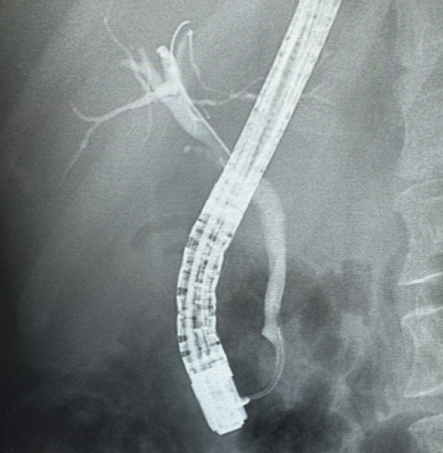

Vias Biliares e Pâncreas

A via biliar tem papel importante no transporte das substâncias produzidos no fígado para serem levadas no intestino delgado para ajudar na absorção dos nutrientes.

O Pâncreas tem dupla função tanto exócrina na produção de enzimas importantes na absorção, bem como uma parte endócrina de vários hormônios sendo o mais conhecido a insulina na regulação da nossa insulina. Suas patologias também inflamatórias sendo da via biliar a mais conhecida os cálculos biliares e do pâncreas com a pancreatite aguda e crônica muitas vezes relacionado ao uso de álcool.